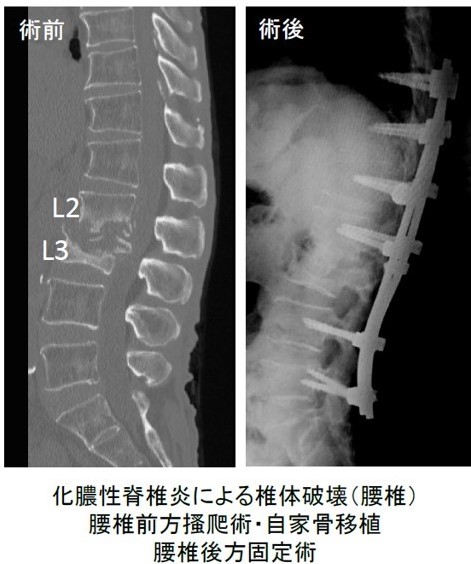

神経症状が悪化する場合、脊柱変形が進行・悪化する場合は、適切な手術を受けることが望まれます。特に、画像診断で膿瘍(細菌感染が膿(うみ)を形成した状態)を認める場合には、早々に手術を考慮しなければなりません。脊椎骨の安定が損なわれた場合、あるいは薬物治療では治癒できない場合なども手術が必要となります。